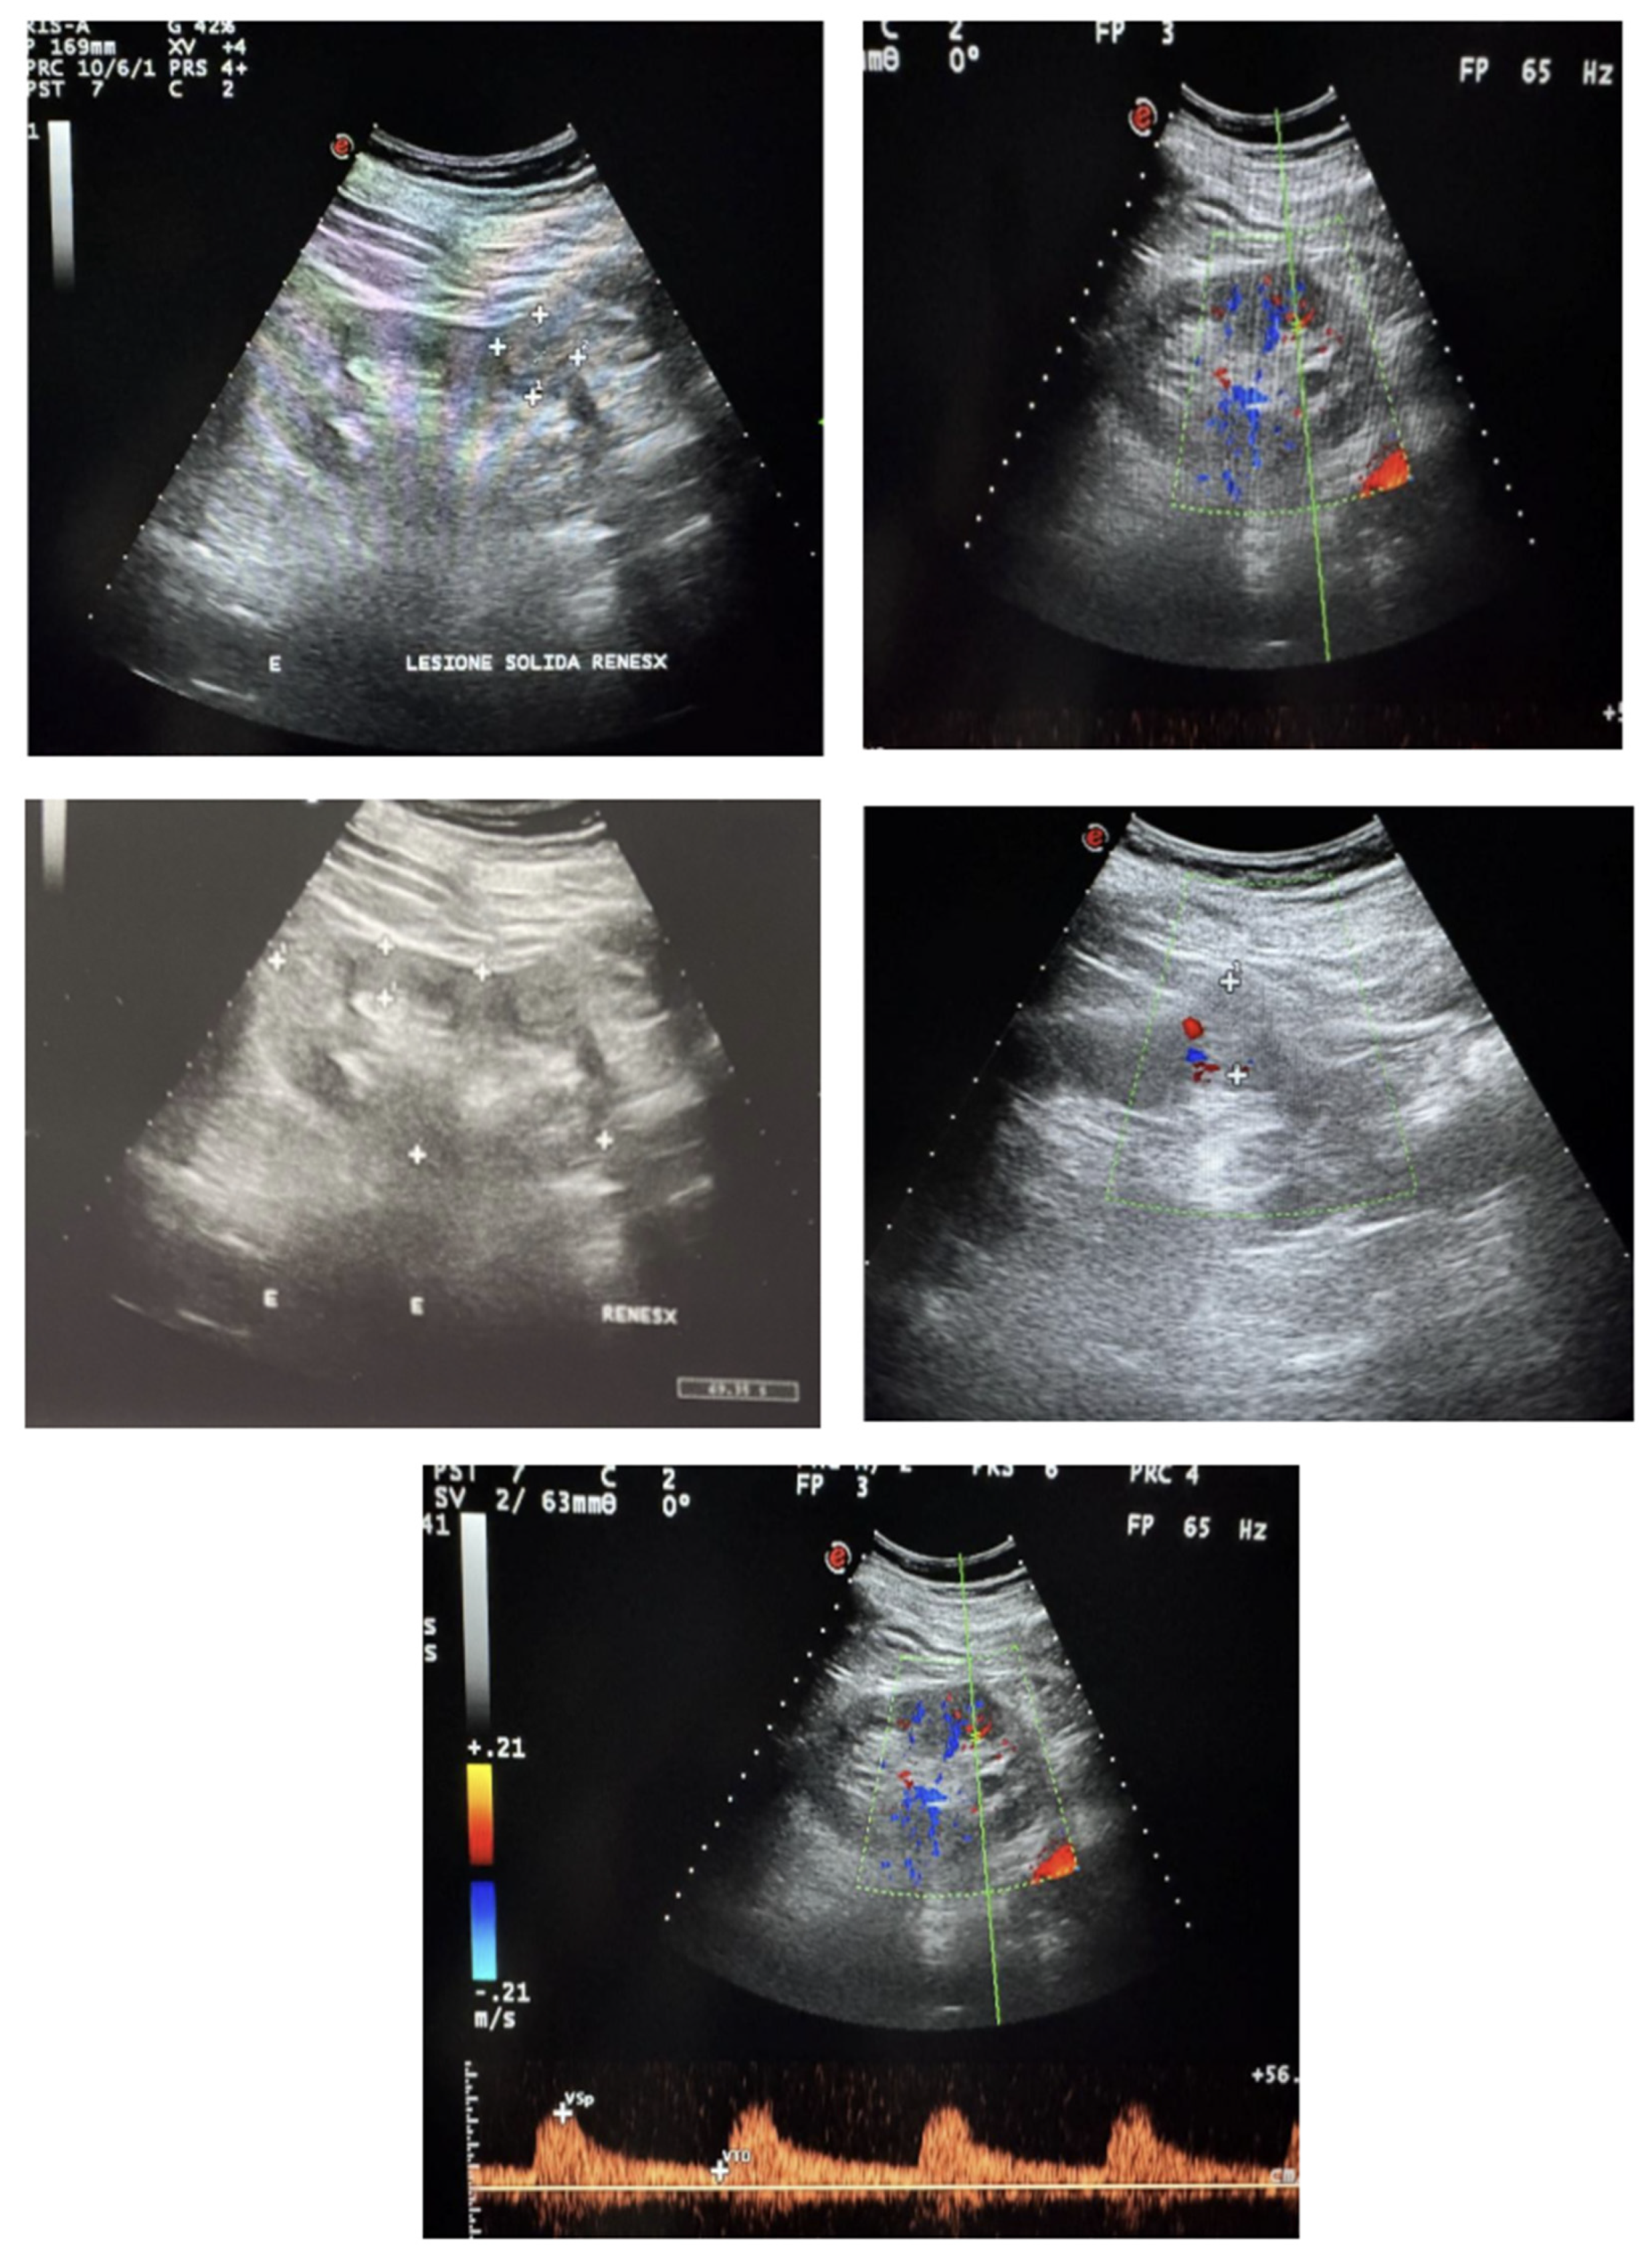

2. Case Presentation

5.1. Ultrasound Evaluation